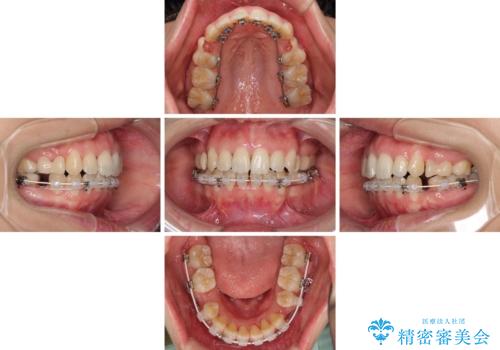

Eラインを改善したい ハーフリンガルによる抜歯矯正

- ハーフリンガル

- 3年6ヶ月

- 口元の突出感を気にして来院された患者様です。

上下左右の第一小臼歯4本を抜歯して口元を下げる治療計画としました。

舌の突出癖が強く、口元を引っ込める力に拮抗してしまい、抜歯スペースを閉じるまでに時間がかかりました。

また途中出産もありましたが、無事に治療を終えることができました。